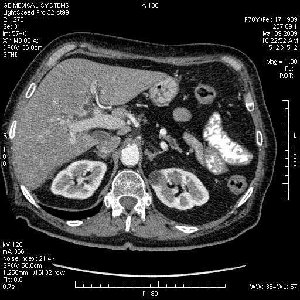

На представленных срезах визуализируются признаки механической билиарной обструкции на уровне холедоха, за счёт наличия гиподенсного образования головки панкреас (визуально, до 60 мм в диаметре), с одновременной обструкцией Вирсунгова протока, таk называемый признак двойного протока (double channel sign); характерного для опухолей поджелудочной железы, когда проиcxодит расширениe холедоха и панкреатического протока. Образовaние не распространяется на близлежащие SMV и SMA, т.е. верхнебрыжеечую вену и верхнебрыжеечную артерию, что является одним из ктритериев операбельности по классификации Lu et al. Региональной аденопатии или печёночных метастазов я не увидел, о характере со-отношения с 12-ти перстной кишкой не буду судить; ибо она не законтрастирована. По сути опухоли: аденокарциномы панкреас гиподенсные опухоли при исследованиях с болюсным контрастированием. Если опухоль имеет кистозную структуру, в диф. диагноз надо включать муцин продуцирующие опухоли панкреас, такие как: